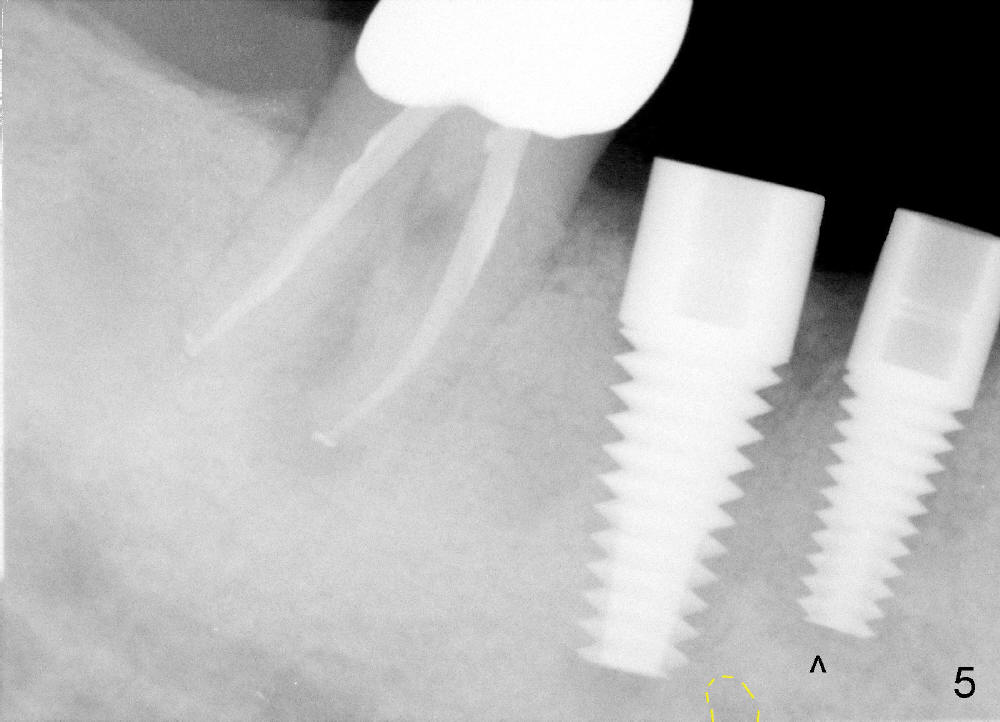

One month after implant placement at the sites of #29,30, the former is found loose (Fig.1,2). It is placed higher than #30. Three weeks later, PA is retaken to confirm that there is space apical to the implant at #29 (Fig.3 double arrows) and that there is distance from the mental loop (yellow dashed line). After infiltration anesthesia, the implant is torqued down initially (compare Fig.4,5) and more (Fig.6,7). To prevent re-loosening, the two implants are splinted (Fig.8).